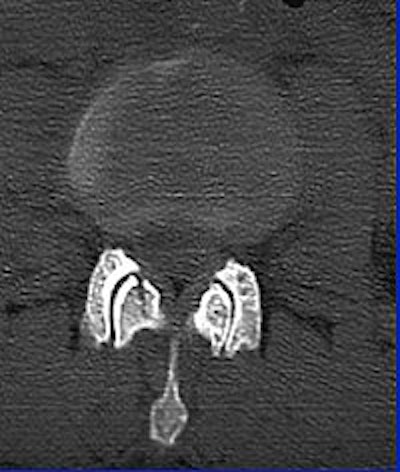

Whichever model is chosen, Cinnamon advised paying attention to the inverse relationship of contrast and spatial resolution, using the following case as an example (images F-G).

![]() |

| Image F |

"On the 2.5-mm slice, you can see the occipital condyle fracture. If (you) go down to the 0.5-mm slice, you can see the fracture just as well -- maybe it looks a little sharper. But you can still identify the fracture on the thicker slice. The value for this is on the coronal and sagittal reformatted images from the 2.5-mm axials. There's a tremendous amount of stair-step artifacts. On the 0.5-mm images, you've eliminated the stair-step artifact because your spatial resolution is so good."